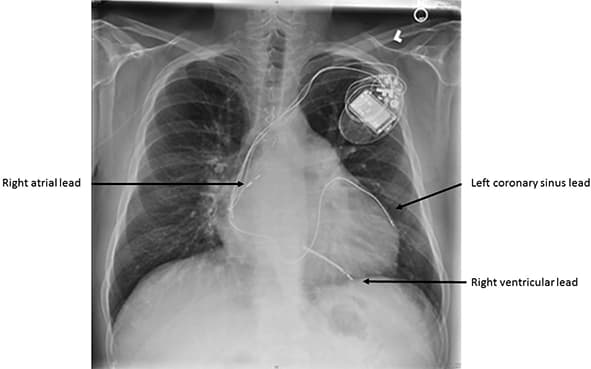

Ugrađuju se kod određene grupe bolesnika sa srčanom slabošću koji imaju oslabljeno srce i električno asinhronu stimulaciju leve i desne komore (električno kašnjenje) usled čega nastaje i mehanička asinhronija/kašnjenje, koja dovodi do srčanog popuštanja (srce kao pumpa je značajno oslabljeno). Ugradnjom ovog pejmejkera se sinhrono (skoro istovremeno) električno stimulišu leva i desna komra, što kod oko 60% bolenika dovodi do oporavka srčane slabosti u manjoj ili većoj meri, nekada i do potpnog oporavka srca kao pumpe.

Kako se ugrađuje pejsmejker

Operacija se standardno izvodi u lokalnoj anesteziji. Sam pejsmejker je generator koji proizvodi struju i ugrađuje se ispod kože. Najčešće sa leve strane, ispod leve ključne kosti, pejsmejker se stavlja u prethodno pripremljen „džep“ pod kožom. Elektrode se plasiraju kroz odgovarajuće vene, pod kontrolom rendgena, do srca, tačnije do desne komore i pretkomore, a u slučaju resinhronizacionog pejsmejkera, elektroda za stimulaciju leve komore se plasira kroz površne vene na srcu (coronarni sinus). Kada se konstatuju zadovoljavajući električni parametri, elektrode se „ušrafljuju“ u srčani mišić.

Ugradnja antibradikardnog pejsmejkera i defibrilatora traje 40-60 min kada su sve strukture anatomski na svom mestu. Ugradnja resinhronizacionog pejsmejkera traje nešto duže.